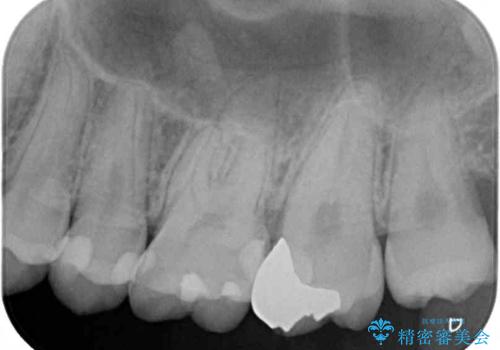

- 奥歯にフロスが引っかかるようになり、虫歯ではないかとのことで来院された患者様です。

レントゲン写真より、左右奥歯にむし歯があることが分かりました。

奥で目立たないことから、虫歯の再発リスクが最も低く、咬合力による歯への負担も少ないゴールドインレー(PGAインレー、白金加金インレー)にて修復治療をすることとしました。

ゴールドインレーは銀歯のインレーやセラミックインレーと比べ、「技工操作の精度が高く、適合が著しく良い」というメリットがあります。特に上の奥歯は歯科医師の操作が行いにくいため、「適合の良さ」は再治療のリスクを防ぐ上でとても重要な要素となります。